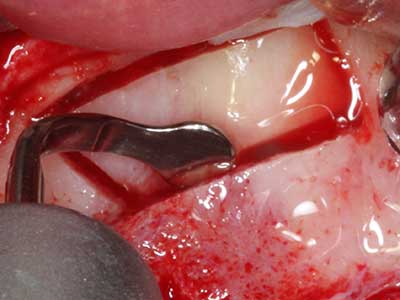

Piezosurgery has additional advantages when harvesting bone blocks. In addition to the high precision with osteotomy described above, the use of the thin saw tips specifically minimizes loss of material. Greater loss of material during harvesting can be expected with the thicker instrument tips, particularly when using Lindemann drills (Lakshmiganthan, Gokulanathan et al. 2012). The basal separation, which is necessary particularly for retromolar block transplants, is simplified by specially designed rectangular saws, with the result that piezosurgery is viewed as a precise, simple and safe procedure for harvesting retromolar bone blocks (Happe 2007) (Fig. 1-12).

Fig. 1: Preparation of a bone cover with the Piezomed (W&H Salzburg, Austria).

Fig. 3: Basal separation of the block is easier with specially angled attachments.